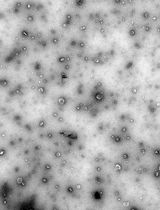

In Situ Crosslinking of Bioorthogonal Nanoparticles to Restore Clot Stability in Coagulopathic Blood

原位交联生物正交纳米颗粒以恢复凝血障碍血液中的血栓稳定性